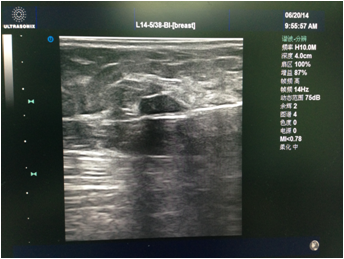

先由主刀医生行彩超检查,和患者确认及核对拟切除的目标病灶。消毒铺巾后医生在彩超引导下于表皮,手术路径及目标病灶周围注射局麻药(图1)。麻醉满意后于彩超引导下进旋切针到目标病灶下方,然后开始切除目标病灶(图2)。最后加压包扎,切除的病灶送病理检查(图3)。整个手术过程于局麻下完成,会有轻微疼痛,但一般程度不重。

图3 切除后的肿物。